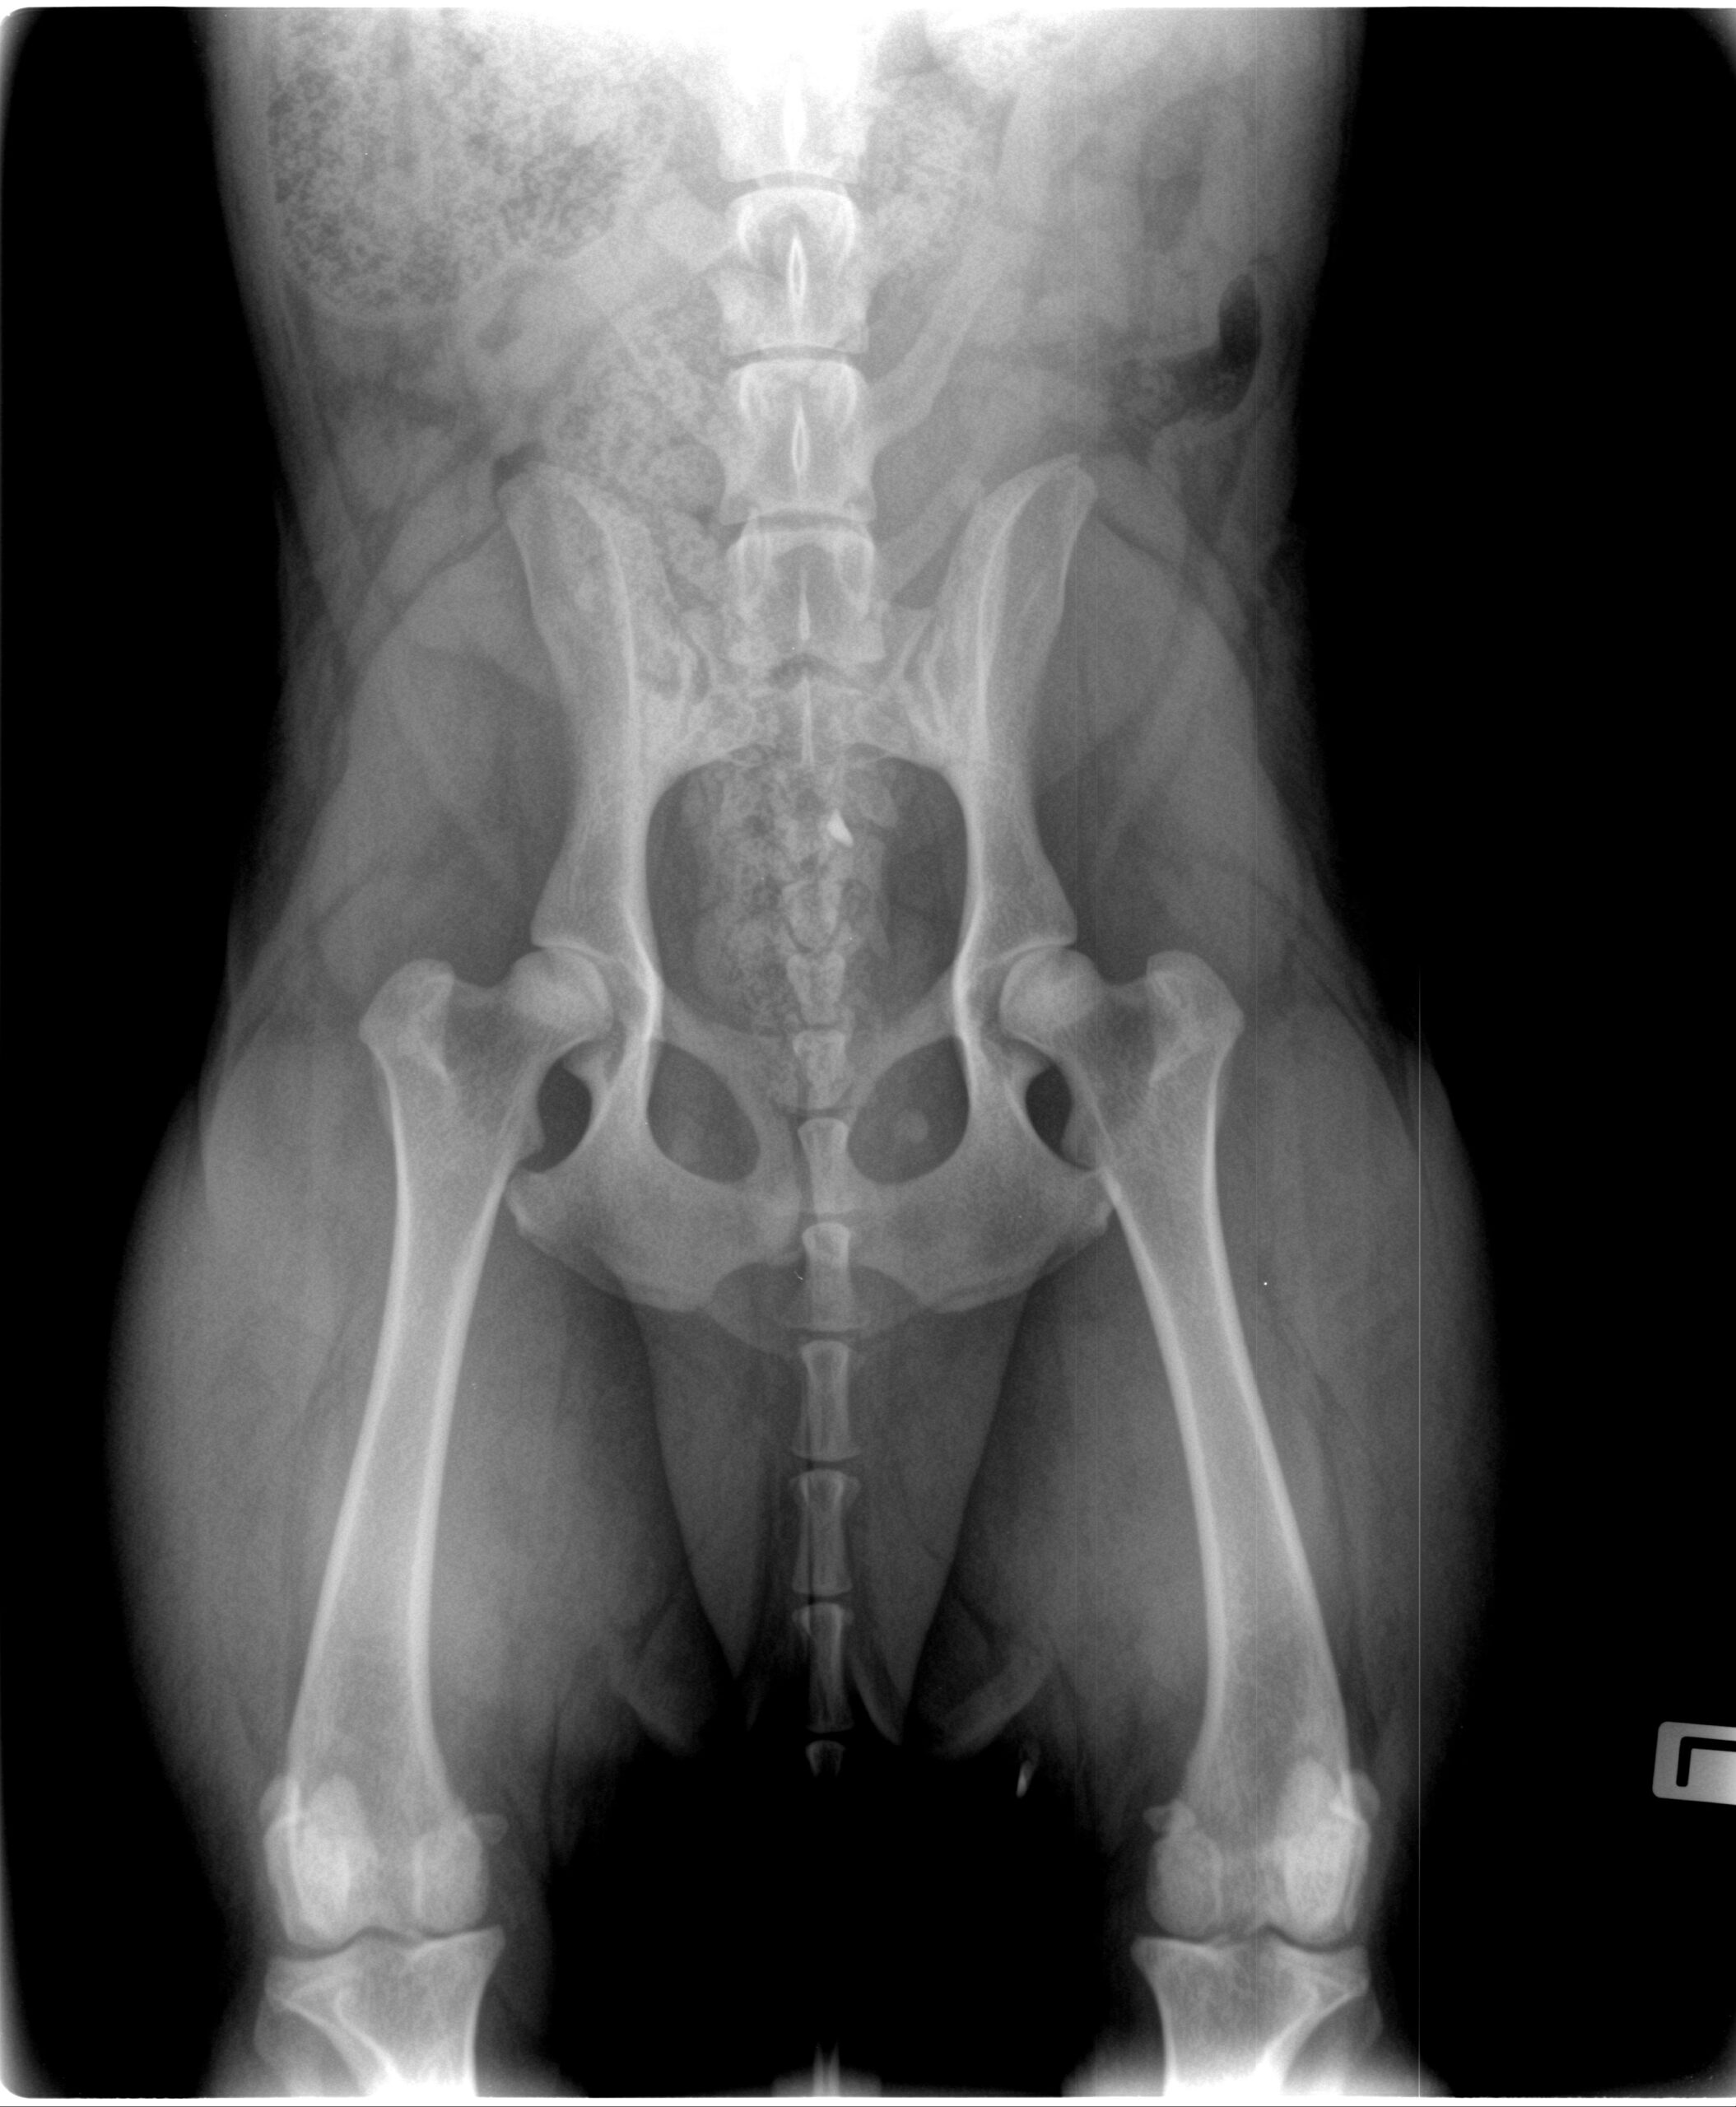

Hüftgelenkdysplasie (HD)

B1/C1

Röntgenaufnahmen

Ausgewählte Röntgenaufnahmen geben einen ergänzenden Einblick in die orthopädischen Untersuchungen dieses Zuchthundes. Die offiziellen Ergebnisse zu HD und ED finden Sie in der Übersicht oben. Weitere Nachweise stellen wir bei ernsthaftem Interesse gern zur Verfügung.